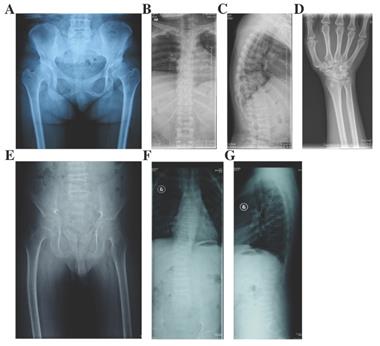

Figure 5

Radiographs of the probands with EDMMD and Kniest dysplasia. A-D: X-rays of pelvis (A), spine (B and C) and hands (D) of the proband in Family 9 with EDMMD. Osteoarthritis, coxa vara, shortening femoral necks and sclerosis of acetabulums were obvious in pelvis. Biconcave deformity, rough edges of vertebral body and narrow intervertebral disc spaces were significant in spine. Narrowing of the metacarpophalangeal and interphalangeal joint spaces and expansion of metaphyses were showed in hands and long tubular bones. E-G: Radiographs of pelvis (E) and spine (F and G) of the proband in Family 10 with Kniest dysplasia. Irregular shapes of femur heads, narrow joint space of bilateral hips, flat acetabular roof, coxa vara, severe multiple platyspondyly and slight scoliosis were showed.

In Family 9, the 32 year-old female proband (Ⅱ-1) had the height of 135 cm (<-3SD) (Fig. 2). Her growth was delayed since birth. She came to our department for pain in lumbar vertebra, and the swelling in both lower extremities from 15 years old. Moreover, she had myopia and complained the hearing loss of the right ear (Table 1). X-rays of pelvis showed narrow joint space of bilateral hips, coxa vara, shortening femoral necks and sclerosis of acetabulums. Radiographs of spine showed multiple thoracolumbar vertebras with biconcave deformity, rough edges of vertebral body and narrow intervertebral disc spaces. X-rays of hands displayed narrowing of the metacarpophalangeal and interphalangeal joint spaces and expansion of metaphyses in hands and long tubular bones (Fig. 5). There were no additional affected family members in this family.

Kniest dysplasia

In Family 10, the male proband (Ⅱ-1) was 12 years old, and 130.5-cm tall (<-2SD) (Fig. 2). From the age of eight, the proband complained for the pain in hip joints and lumbar vertebra. No abnormalities were found in his hearing, vision, and mental development (Table 1). X-rays demonstrated irregular shapes of femur heads, narrow joint space of bilateral hips, flat acetabular roof, coxa vara, severe multiple platyspondyly and slight scoliosis (Fig. 5). The father of the proband (Ⅰ-1) was 35 years old and 141.3-cm tall (<-3SD) but the mother of the proband (Ⅰ-2) was normal.